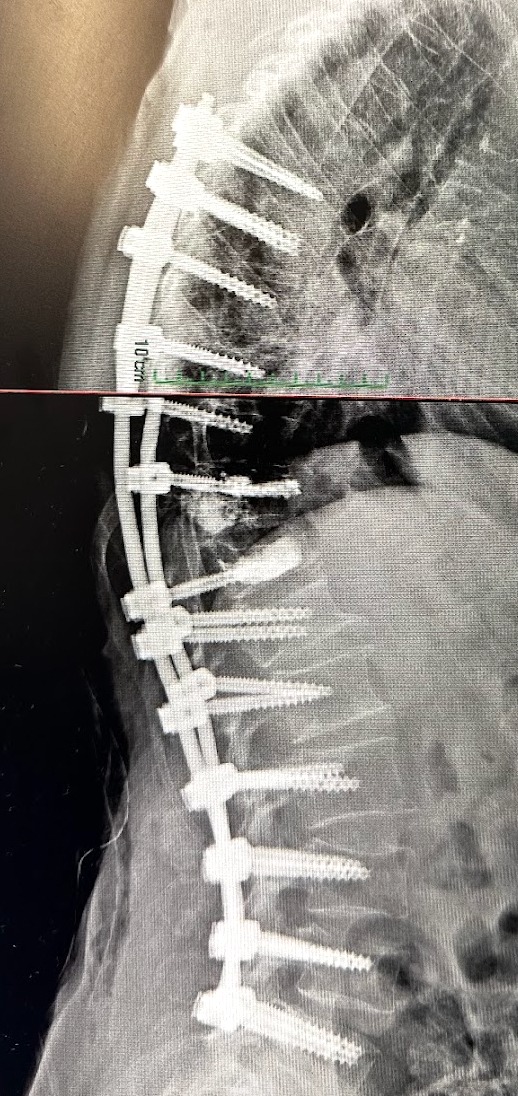

Dr. Vito Lavanga

Ortopedia della Colonna Vertebrale